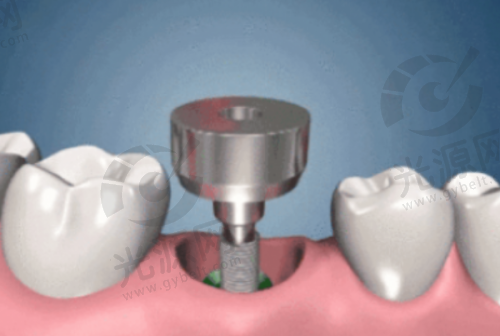

二、诺贝尔种植牙的技术优势与医生水平

诺贝尔种植牙在技术上引入了领跑的微创手术理念,较大限度减少患者的疼痛和术后修复时间。医院的种植牙医生均接受过专精的国内外培训,并持有相关资质证书。例如,诺贝尔的Active系列种植体因其独特的螺纹设计和亲水性表面,能与骨组织快速结合,提供出色的初始稳定性,极大提高了种植成功几率。此外,医院根据每位患者的具体情况,制定个性化的种植方案,确保治疗的针对性和有效性。特别多患者在接受种植手术后的反馈中表示,术后的修复非常快,成效非常自然,这得益于医院采用的高端技术和设备。通过不断的技术创新和学术交流,诺贝尔口腔医院的种植牙服务赢得了患者的高度认可,许多患者表示愿意推荐给身边的朋友和 family。